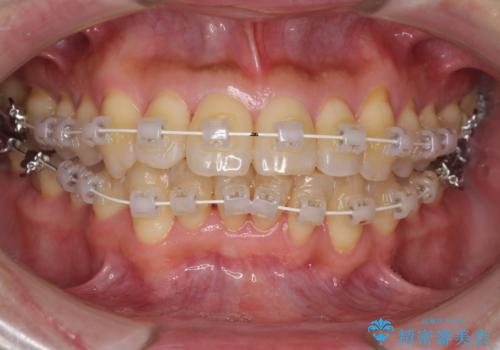

- 矯正装置

- 審美装置

治療開始の頃は、食事や歯磨きが慣れず、装置が頻繁に脱落しましたが、2,3ヶ月ほどで慣れ、その後は1年ほどで治療を終えることができました。